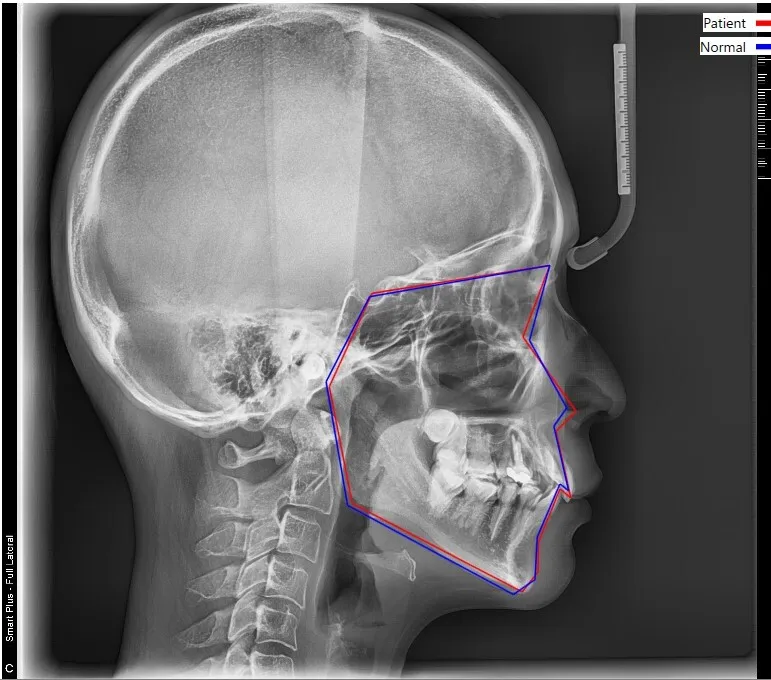

矯正の診断で大切なセファロレントゲン撮影とは?

セファロ撮影とは?

セファロ撮影とは、矯正歯科の診断に特化したレントゲン撮影法です。そのため、一般的な歯科医院には設置されていない場合が多いのが実情です。

しかし矯正治療を行う上では必須の検査であり、日本矯正歯科学会でも診断時に必ず実施することが推奨されています。

セファロ撮影

セファロ撮影の方法

撮影方法としては、頭全体を横向きに撮影します。その際、撮影する患者さまの頭の位置・方向は厳密に規格化されており、耳に「イヤーロッド」と呼ばれる器具を挿入して位置を固定します。これにより、同じ条件下での撮影が可能となり、日付や場所が異なっても治療経過の比較が正確に行えるというメリットがあります。

撮影後の解析と得られる情報

撮影後には数十の計測ポイントをもとに100以上の数値が得られ、以下のような診断が可能となります。

① 前後的関係の分析

頭部全体に対して、上下の顎の前後的位置関係を評価します。

• 上顎が突出している場合

• 下顎が後退している場合

• 歯の傾きによるもの

原因が異なるため、治療方針も異なります。また、数値が大きくずれている場合には外科矯正が必要になることもあります。

垂直的関係の分析

簡単に言えば顔の長さの評価です。この情報により、奥歯の固定方法や治療中の注意点が明確になります。顔の長さに関しては、歯の移動で多少は変化しますが、大きな改善が難しいケースもあるため、数値による判断が重要です。

成長方向の分析

成長期のお子様の場合、上下顎の成長パターンを把握することが重要です。同年代との比較により、正常な発育かどうかを判断します。

• 成長が異常な場合:ヘッドギアなどによる成長コントロールが必要な場合もあります。

• 定期的撮影:お子様は年1回、成人では治療前後などに経時的に撮影を行います。

その他の診断内容

• 臼歯部や前歯の位置関係

• 開咬の程度

• 骨格的バランスなど

総合的な診断と治療計画

当院の矯正歯科治療では、セファロ撮影だけでなく、総合的に分析し一人ひとりに最適な治療計画を立案します。